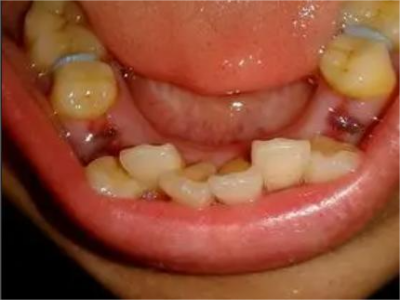

阻生牙是指由于邻牙、骨或软组织的阻碍而只能部分萌出或完全不能萌出,且以后也不能萌出的牙。引起牙阻生的成因,主要是由于颌骨缺乏足够的空间容纳全部恒牙。常见的阻生牙为下颌第三磨牙、上颌第三磨牙及上颌尖牙。

阻生牙可反复引起冠周炎,或引起邻牙牙根吸收和破坏,位置不正,不能完全萌出,好发部位是上、下颌第三磨牙。

阻生牙主要原因是随着人类的进化,颌骨的退化与牙量的退化不一致,导致骨量相对小于牙量,颌骨缺乏足够的空间容纳全部恒牙。